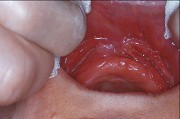

2.組圖為牙瘤的外觀及X 線表現,有關此病的描述錯誤的是  (    )

正確答案:E